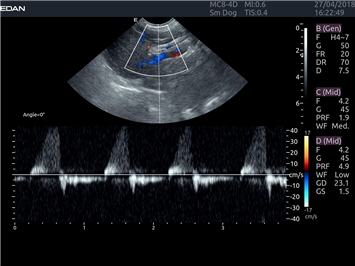

EDAN Acclarix LX4 VET представляет собой профессиональную ультразвуковую систему, специально разработанную для ветеринарных исследований. Сочетание стабильности, высокой производительности и эффективности делает эту систему идеальным выбором для современной ветеринарной практики.

Цветовой допплер:

Да

Импульсно-волновой допплер: